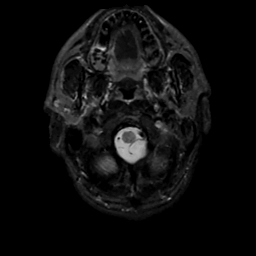

MR Study #1, February 10, 1991 -- Slice #2

[Home][Help][Clinical][Tour 1][Tour 2] Slice 2